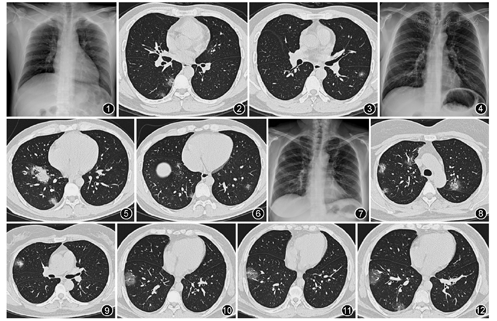

9例患者中3例患者行X线胸片检查,1例无异常,胸部高分辨率CT(HRCT)表现为双下肺多发磨玻璃样渗出影(例1,图1,图2,图3);1例X线胸片表现为右下肺少许渗出影,胸部HRCT表现为双下肺多发磨玻璃样渗出影(例2,图4,图5,图6);1例X线胸片表现为右上肺渗出影,胸部HRCT表现为双上肺多发磨玻璃样渗出影(例3,图7,图8,图9)。所有患者均早期行胸部HRCT检查:其中7例表现为肺部多发磨玻璃影(累及双肺5例,累及单肺2例),累及单肺者在单侧肺内形成多发磨玻璃影(例4,图10,图11,图12),3例在磨玻璃影的基础上伴有状实变(图5,图9);2例胸部HRCT无异常。所有患者均无胸腔积液。

NCP患者早期最重要的影像学特征是胸部HRCT显示为多发的斑片状的磨玻璃影,部分伴有实变。病变常累及双肺,或者累及一侧肺的多个部位。病变常常位于双下肺,也可在双上肺,病变常常位于胸膜下,和中东呼吸综合征(MERS)极为相似,提示COVID-19容易诱发机化性肺炎的可能,为部分患者的治疗提供了一定的理论依据[6]。NCP需要和其他呼吸道病毒引起的肺炎相鉴别。值得注意的是NCP的X线胸片早期可以表现为正常或轻度异常,而胸部HRCT已经有明显的肺炎改变,是"胸片阴性的肺炎"之一[7]。因此应首选胸部HRCT而不是X线胸片作为本病的早期筛查手段。部分患者早期仅表现为发热或呼吸道症状而没有肺炎的影像学表现,尤其注意不要漏诊。